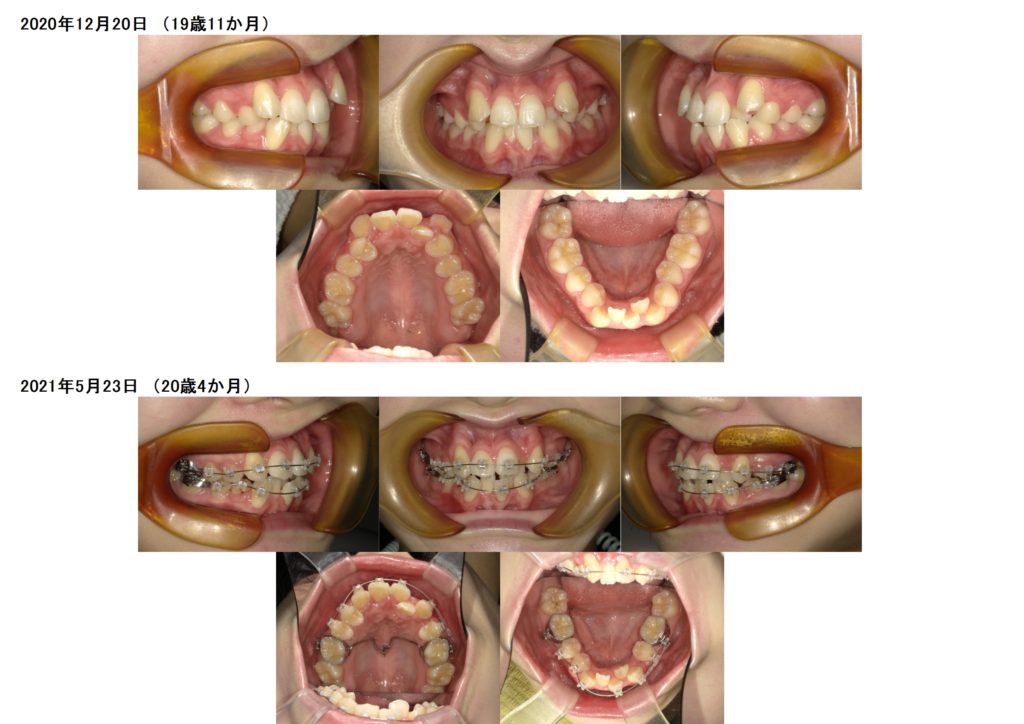

欠損歯がある方の治療例です☆

左側の前歯2番目の上下の歯が欠損です。

裏側にパラタルバーをセットし矯正用のアンカースクリューを上顎に1本埋め込んであります。

上下セルフライゲーションシステムのブラケットを使用しています。

右側の上下4番目の歯を抜歯しました。

どんどん歯は動いていきます☆

とっても早いスピードですよね☺